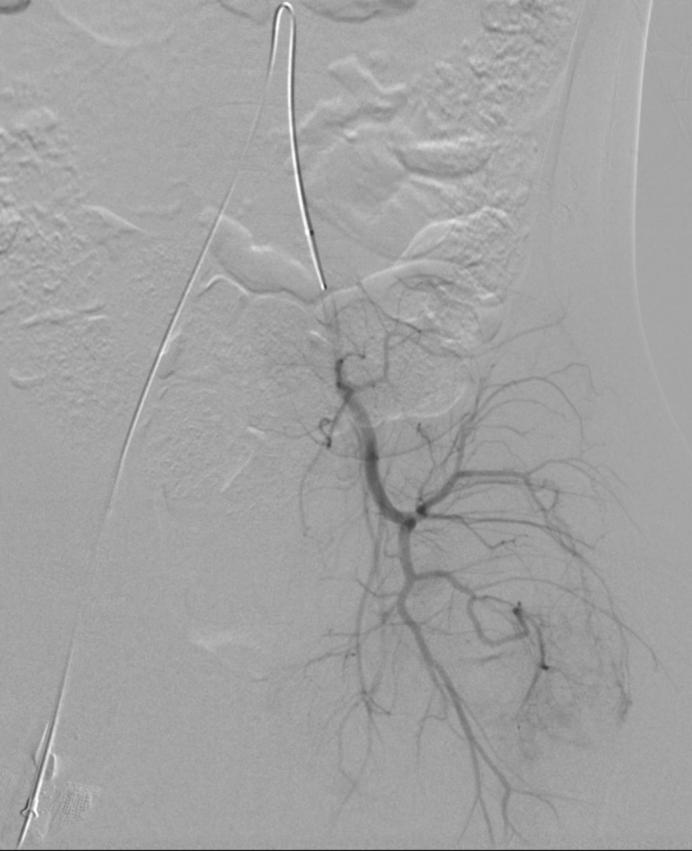

患儿全麻后,进行了经动脉的穿刺造影,可见臀部病灶处可见异常染色,经皮穿刺造影可见病灶处造影剂弥漫分散,诊断静脉畸形明确。进行了硬化治疗。术后第二天出院,出院后口服利伐沙班药物治疗。

经动脉造影提示病灶处异常染色

经皮穿刺病灶处,可见异常染色